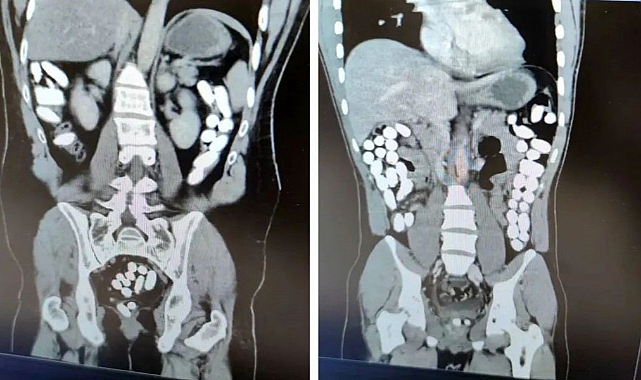

Erzincan polisinin uyuşturucu madde kuryeliği yapan şahıslara yönelik düzenlediği operasyonda, uyuşturucuyu midesine gizleyen İran uyruklu 2 kişi tutuklandı. 2 kilo civarında Afyon sakızı ele geçirildi.  İl Emniyet Müdürlüğü Narkotik Suçlarla Mücadele Şube Müdürlüğü ile Kaçakçılık ve Organize Suçlarla Mücadele Şube Müdürlüğü ekiplerince yapılan çalışmada; Uygulama noktasında durdurulan yolcu otobüsünde yolcu olarak bulunan İran uyruklu A.G. (25) ve E.P. (21) İsimli şahıslara alınan karara istinaden yapılan tomografi çekiminde mide ve bağırsak kısmında uyuşturucu olabileceğini değerlendirilen çokça yabancı cismin olduğu görüldü. Yapılan tetkikler neticesinde A.G. (25) isimli şahıstan 100 parça halinde 847,64 gr gelen Afyon Sakızı, E.P. (21) isimli şahıstan 142 parça halinde 1071,80 gr gelen Afyon Sakızı ele geçirildi. Şüpheliler emniyetteki işlemlerinin ardından sevk edildiği adliyede “Uyuşturucu Madde Ticareti Yapmak” suçundan tutuklanarak cezaevine gönderildi. İHA

İl Emniyet Müdürlüğü Narkotik Suçlarla Mücadele Şube Müdürlüğü ile Kaçakçılık ve Organize Suçlarla Mücadele Şube Müdürlüğü ekiplerince yapılan çalışmada; Uygulama noktasında durdurulan yolcu otobüsünde yolcu olarak bulunan İran uyruklu A.G. (25) ve E.P. (21) İsimli şahıslara alınan karara istinaden yapılan tomografi çekiminde mide ve bağırsak kısmında uyuşturucu olabileceğini değerlendirilen çokça yabancı cismin olduğu görüldü. Yapılan tetkikler neticesinde A.G. (25) isimli şahıstan 100 parça halinde 847,64 gr gelen Afyon Sakızı, E.P. (21) isimli şahıstan 142 parça halinde 1071,80 gr gelen Afyon Sakızı ele geçirildi. Şüpheliler emniyetteki işlemlerinin ardından sevk edildiği adliyede “Uyuşturucu Madde Ticareti Yapmak” suçundan tutuklanarak cezaevine gönderildi. İHA

İl Emniyet Müdürlüğü Narkotik Suçlarla Mücadele Şube Müdürlüğü ile Kaçakçılık ve Organize Suçlarla Mücadele Şube Müdürlüğü ekiplerince yapılan çalışmada; Uygulama noktasında durdurulan yolcu otobüsünde yolcu olarak bulunan İran uyruklu A.G. (25) ve E.P. (21) İsimli şahıslara alınan karara istinaden yapılan tomografi çekiminde mide ve bağırsak kısmında uyuşturucu olabileceğini değerlendirilen çokça yabancı cismin olduğu görüldü. Yapılan tetkikler neticesinde A.G. (25) isimli şahıstan 100 parça halinde 847,64 gr gelen Afyon Sakızı, E.P. (21) isimli şahıstan 142 parça halinde 1071,80 gr gelen Afyon Sakızı ele geçirildi. Şüpheliler emniyetteki işlemlerinin ardından sevk edildiği adliyede “Uyuşturucu Madde Ticareti Yapmak” suçundan tutuklanarak cezaevine gönderildi. İHA

İl Emniyet Müdürlüğü Narkotik Suçlarla Mücadele Şube Müdürlüğü ile Kaçakçılık ve Organize Suçlarla Mücadele Şube Müdürlüğü ekiplerince yapılan çalışmada; Uygulama noktasında durdurulan yolcu otobüsünde yolcu olarak bulunan İran uyruklu A.G. (25) ve E.P. (21) İsimli şahıslara alınan karara istinaden yapılan tomografi çekiminde mide ve bağırsak kısmında uyuşturucu olabileceğini değerlendirilen çokça yabancı cismin olduğu görüldü. Yapılan tetkikler neticesinde A.G. (25) isimli şahıstan 100 parça halinde 847,64 gr gelen Afyon Sakızı, E.P. (21) isimli şahıstan 142 parça halinde 1071,80 gr gelen Afyon Sakızı ele geçirildi. Şüpheliler emniyetteki işlemlerinin ardından sevk edildiği adliyede “Uyuşturucu Madde Ticareti Yapmak” suçundan tutuklanarak cezaevine gönderildi. İHA